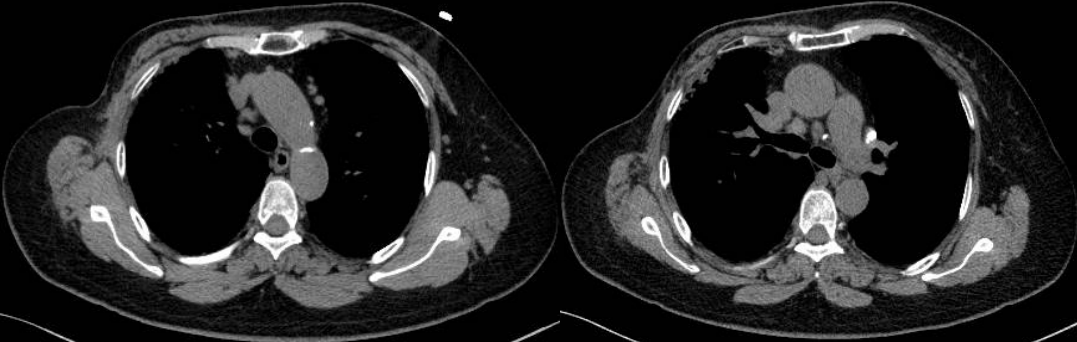

患者8個月后復查胸部CT示:縱隔、雙肺門淋巴結較前明顯縮小,較大者約1.4×1.1cm。